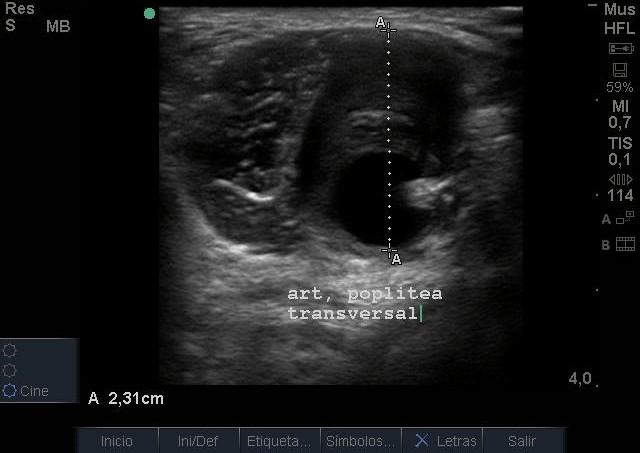

Se visualiza aneurisma de 2 centímetros con imagen compatible con trombo intramural. En modo Doppler flujo turbulento. Realizamos ecografía de rodilla contralateral y aórtica sin hallazgos reseñables.

Juicio Clínico: Aneurisma poplíteo con trombo intramural.